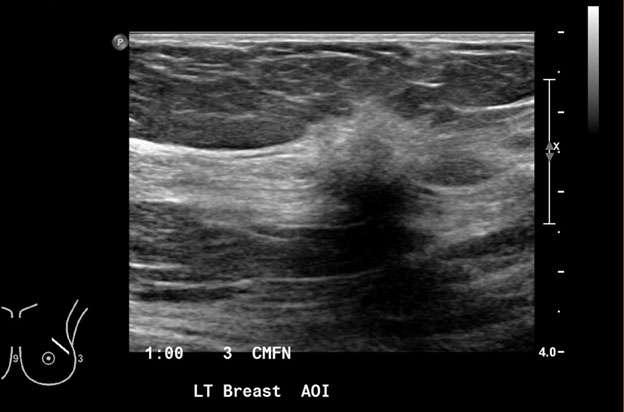

2. Round: a round mass (Figure 2) is spherical, ball-shaped, circular, or globular in shape.

Mammography: Masses Figure 2

Figure 2: A) On Mammogram rim-calcified round mass was noted in the right breast at 7 o'clock, lower outer quadrant located 1 centimeter from the nipple (white arrow). B) Ultrasound demonstrates a round mass with peripheral hyperechogenicity measuring 10 x 7 x 10 mm in the right breast at 7 o'clock located 1 centimeter from the nipple, favoring fat necrosis. BI-RADS Category: 2.